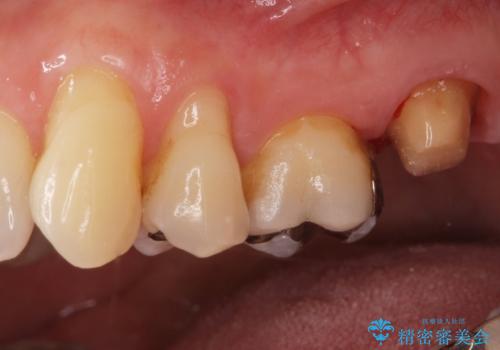

被せ物、古い材料を徹底的に除去し、ラバーダム防湿にて無菌的処置を行い、セラミックの被せ物で治療を行いました。

治療が終了してからも定期的にレントゲンをとり経過観察を行いました。

病巣は現在縮小しておりまた白い被せ物が入り患者様に満足してもらえました。